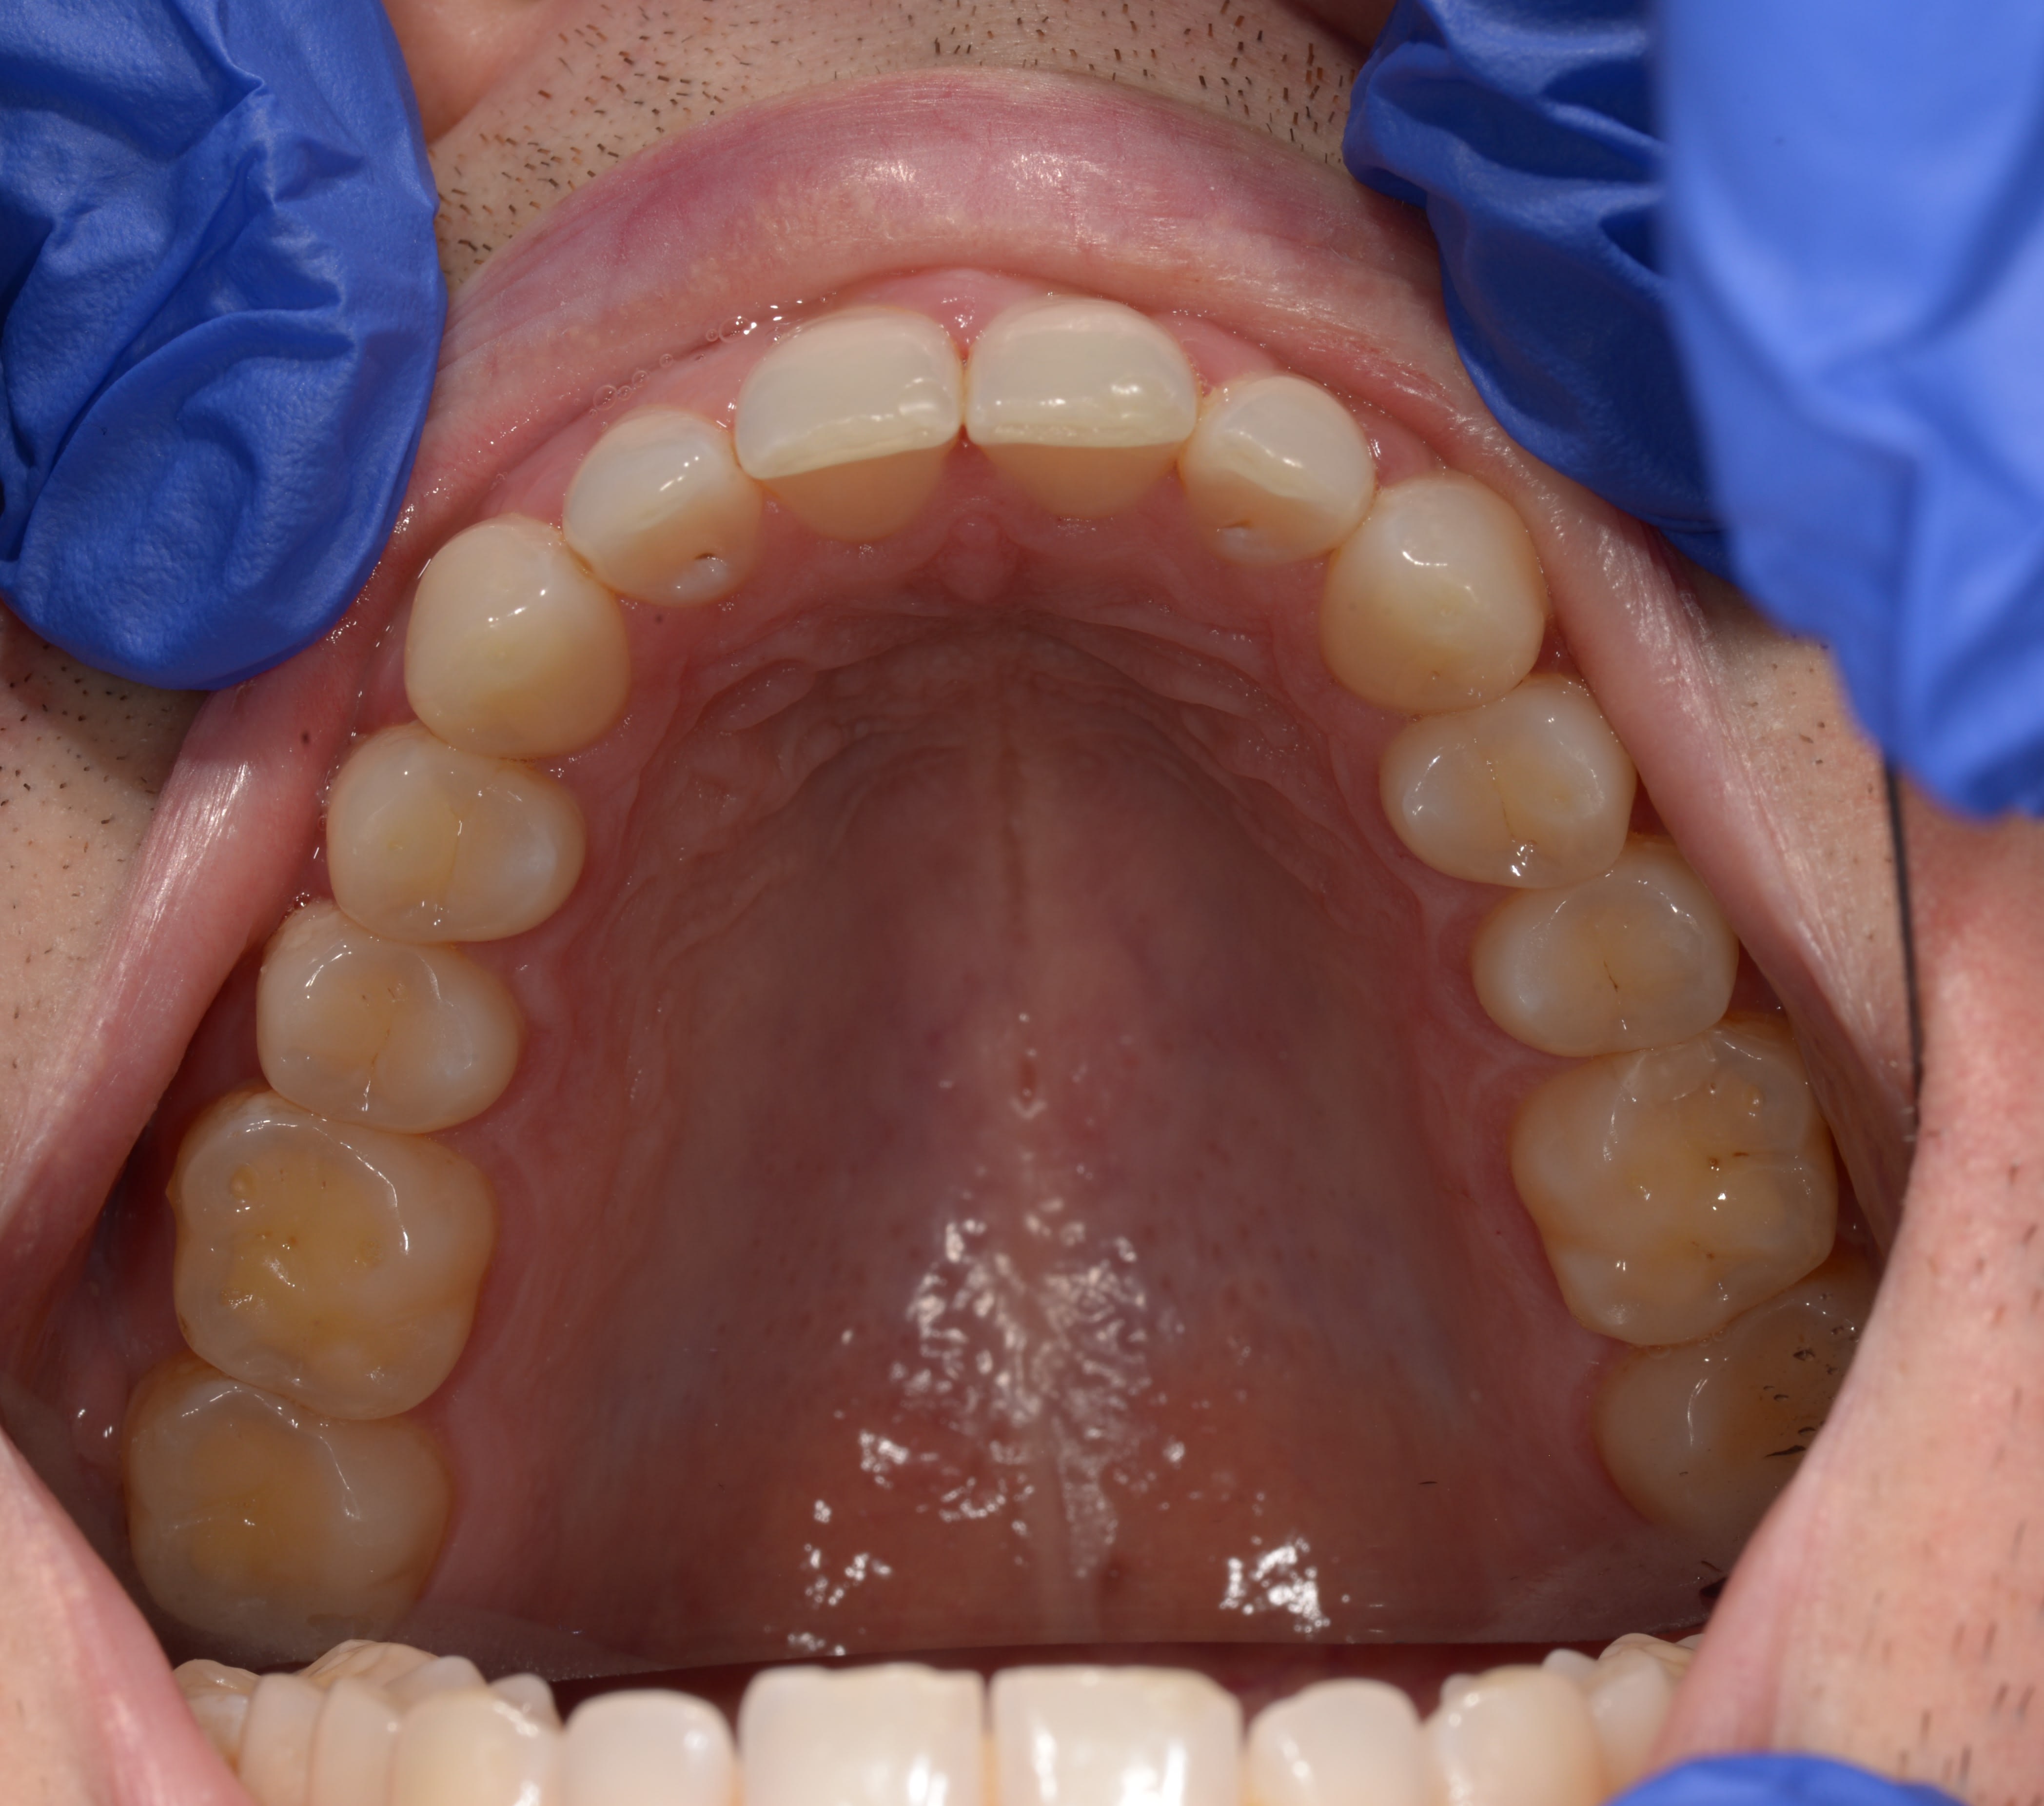

Que proposer à mon patient de 31 ans, pratique sportive régulière (juste de l'eau, rarement du sucre), non fumeur, avec une usure assez marquée des molaires (a priori je dirai des usures d'origine chimique associée à du bruxisme) dont je vous joins ici les photos.

Les molaires étaient sensibles il y a quelques mois à l'alimentation, mais depuis la fluoration et l'utilisation de dentifrice adapté (Mirasensitive HAP+), les sensibilités apparaissent uniquement lorsque j'utilise une sonde exploratrice sur la face occlusale.

Les usures évoluent sensiblement d'année en année (suivi photo).

Je vous joins les photos

J'ai modifié les photos, j'avais posté 2x la machoire supérieure, mais pas l'inférieure qui est plus usée, nott sur 36. J'en rajoute un peu en voila dautres.

Pour moi j'étais certain du diagno de RGO, vu les faces occlusales, et vu les faces incisales des 42 à 32.